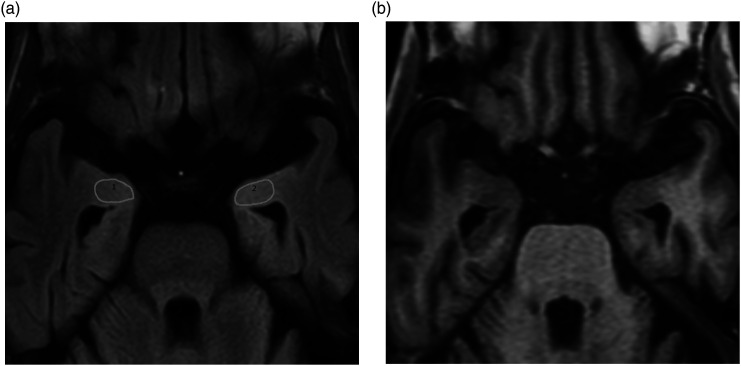

Material and methods: Patients with pAD (n = 47; age range = 68-93 years, mean = 80.8 ± 6.7 years; 14 men and 33 women) who underwent T2W-FLAIR imaging and MR morphometric study using a voxel-based specific regional analysis system for AD (VSRAD) were retrospectively examined. To measure signal intensity ratios of the left to right PC&A (L-PC&A/R-PC&A), regions of interest (ROIs) were set on the transaxial images in which both PC&As were most broadly depicted; the ROIs were defined as large as possible. Correlations between the L-PC&A/R-PC&A and medial temporal lobe cortical atrophy (MTLCA) as well as whole cerebral cortical atrophy (WCCA) on VSRAD were determined. Correlation between the L-PC&A/R-PC&A and age was also determined.

Abstract Image